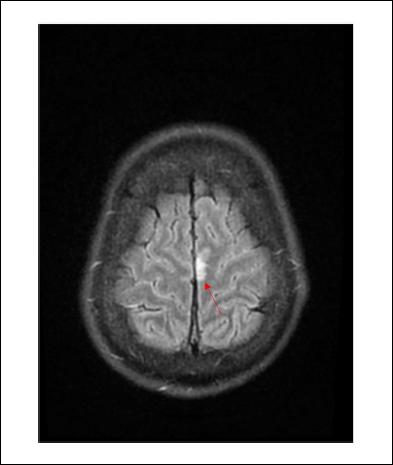

De la valoración neurológica se destaca: electroencefalograma (EEG) al ingreso sin actividad epileptógena, resonancia nuclear magnética (RNM) signos de meningitis a nivel frontal parasagital bilateral (Figuras 1 y 2), cerebritis a nivel de hemisferio cerebeloso izquierdo, sin otras complicaciones. Se otorga alta de terapia intensiva a los 7 días con buena evolución y sin secuelas.